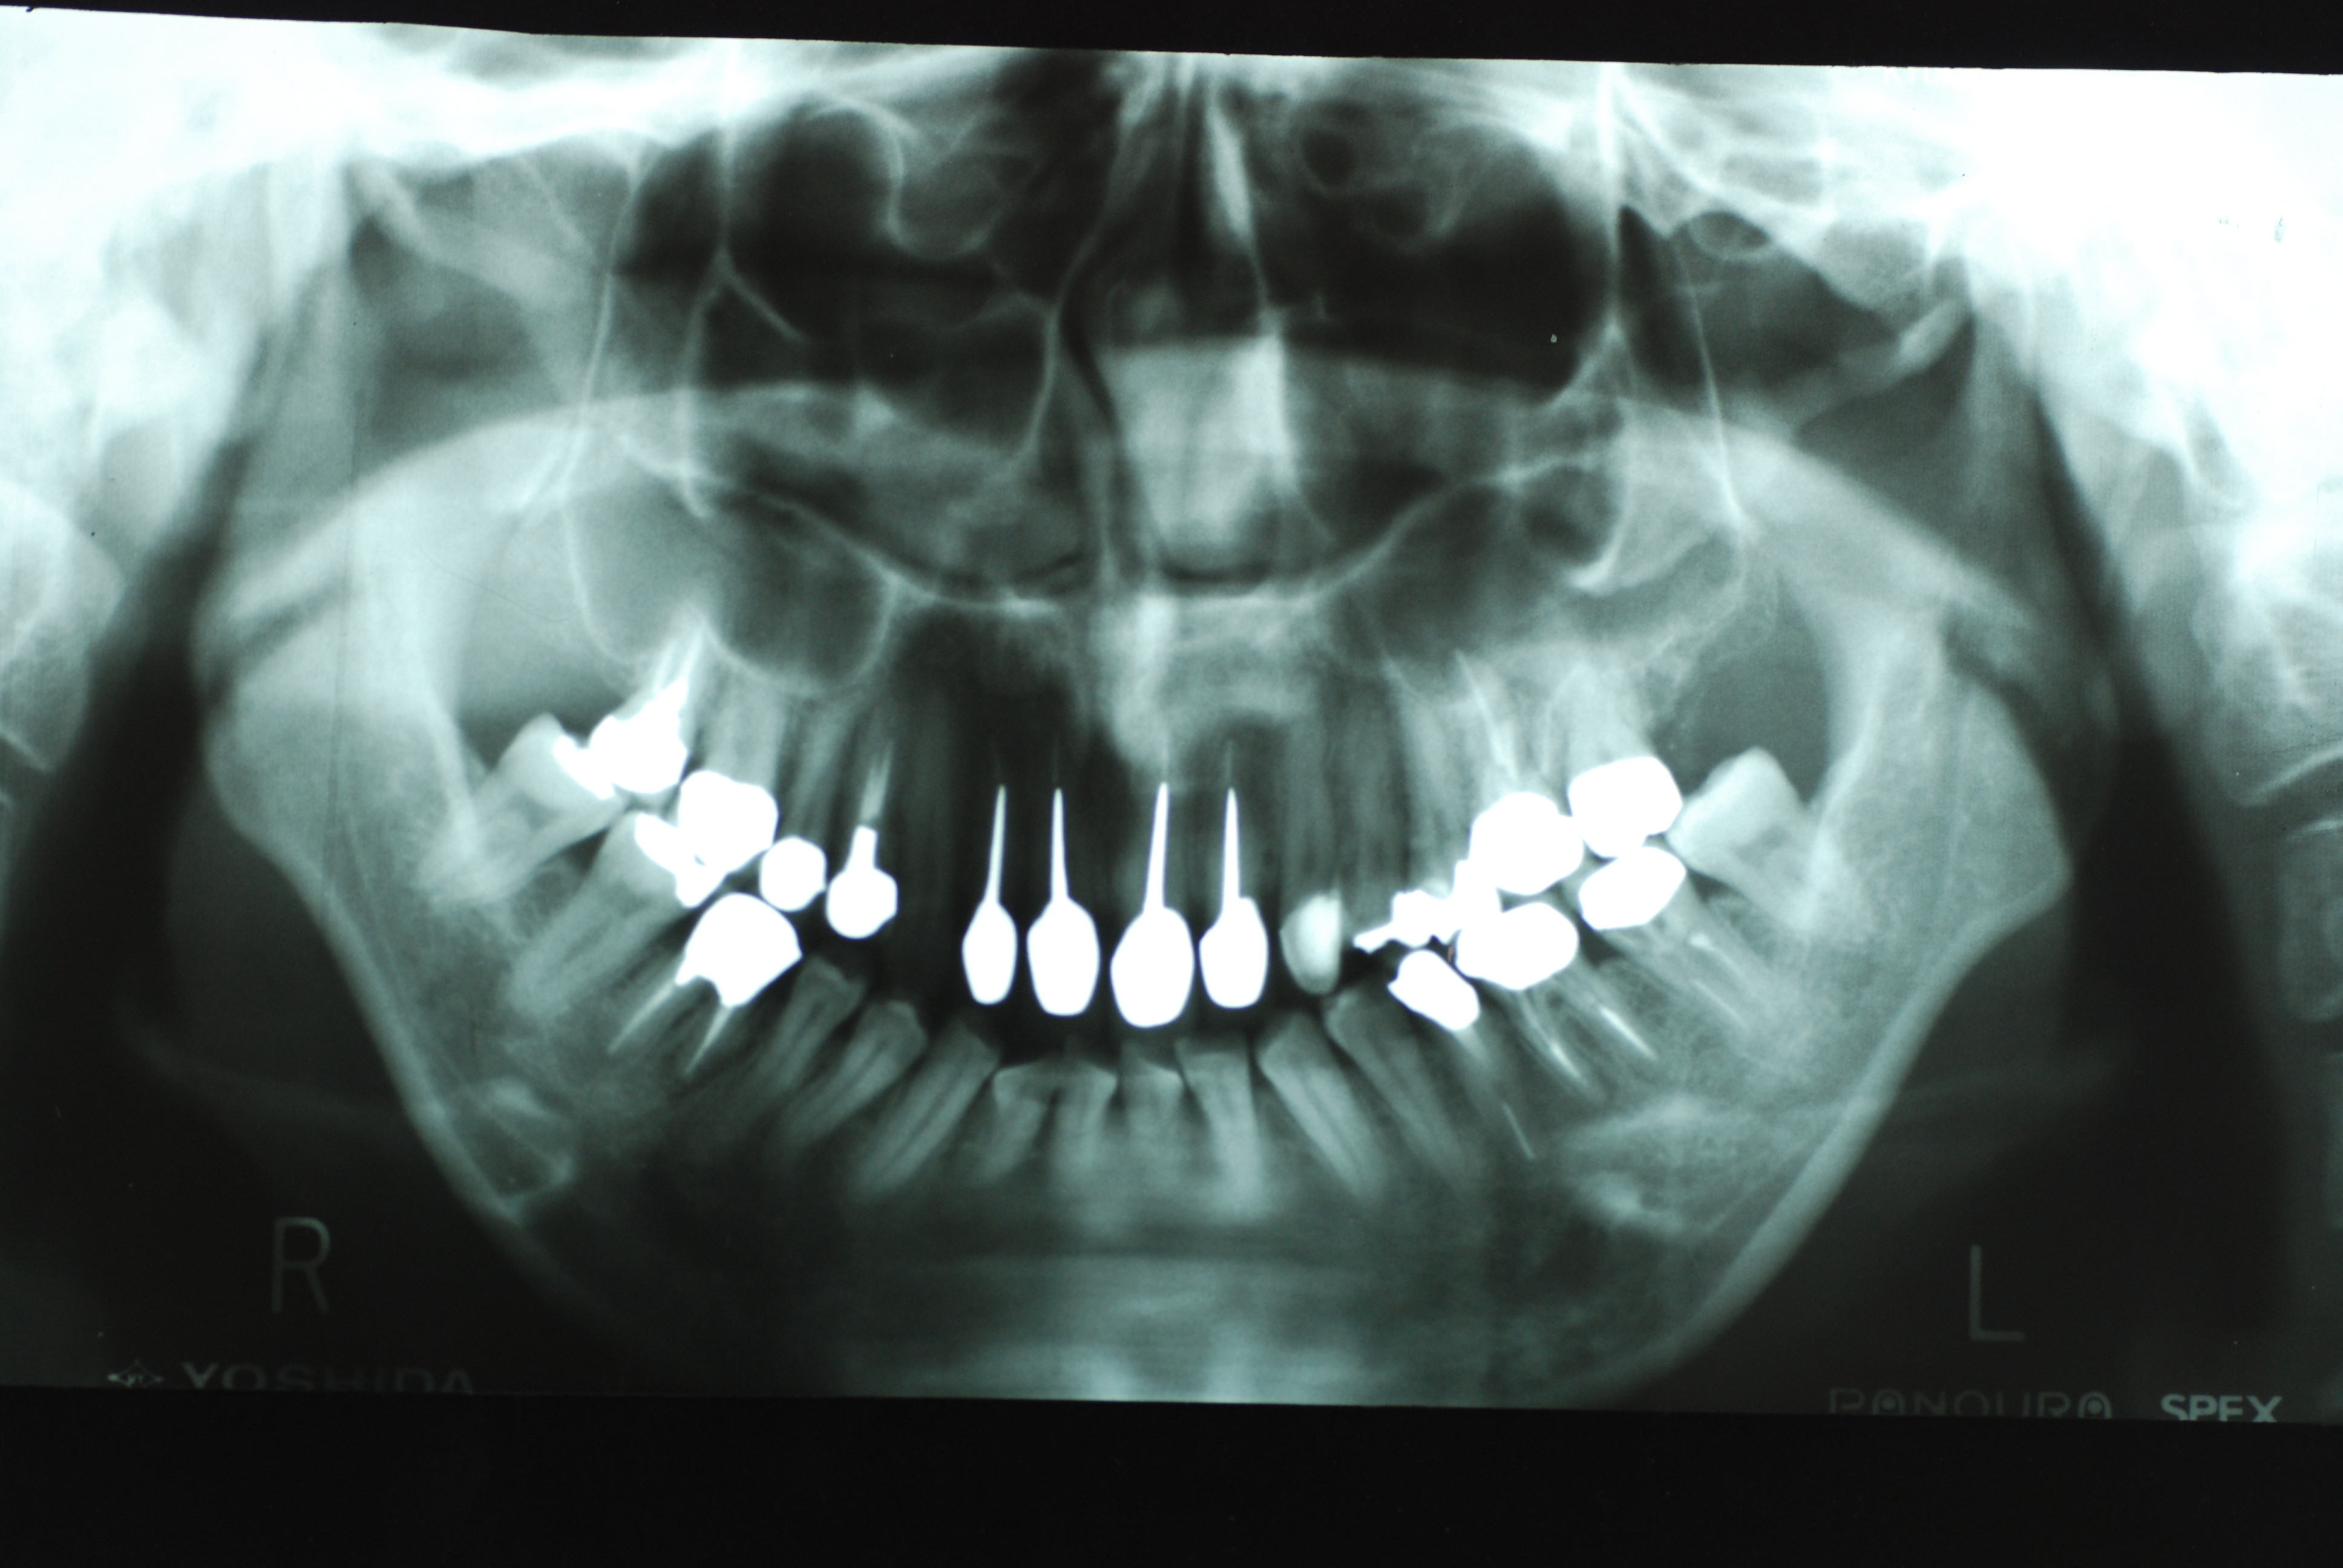

左下の一番奥の歯の治療がいい加減なようです。

そして歯周病を併発していて別の歯科医院で抜くしかないと言われて何とかならないかと当院に来られました。

左下の一番奥の歯の治療がいい加減なようです。しかし治療をしてみると滅菌しながら治療をすることの困難さを痛感しました。

三本ある根管の内、難しい手前の根幹の治療が為されていません。顎の骨に黒い影ができています。

骨の部分は健康を回復しています。影がありません。治療が成功しています。

反対側の大臼歯には分岐部に深い虫歯と深い分岐部病変がありますが、虫歯の治療後は歯周病が酷いのに来られなくなりました。

上のレントゲンでも歯根の間に影があります。悪性の分岐部病変ですね。